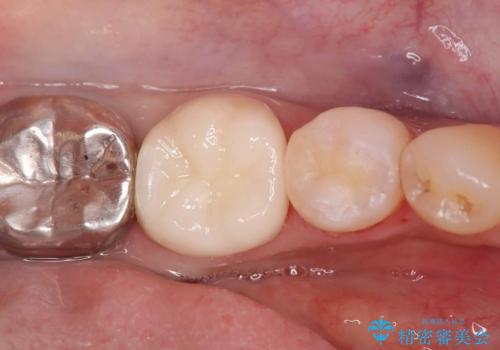

- 銀歯の下の虫歯です。お写真で分かるように広範囲で深い虫歯でした。

1歯はオールセラミッククラウンもう1歯はセラミックインレーで治療を行いました。

- 税込209,000円(オールセラミッククラウン121,000円+仮歯11,000円+セラミックインレー77,000円)費用は治療当時の料金となります